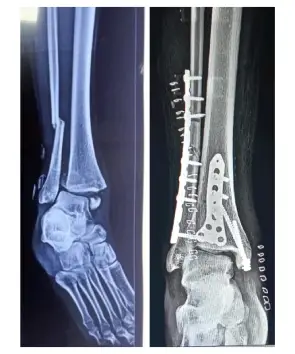

Dr. Keerthivasan Contact number WhatsApp